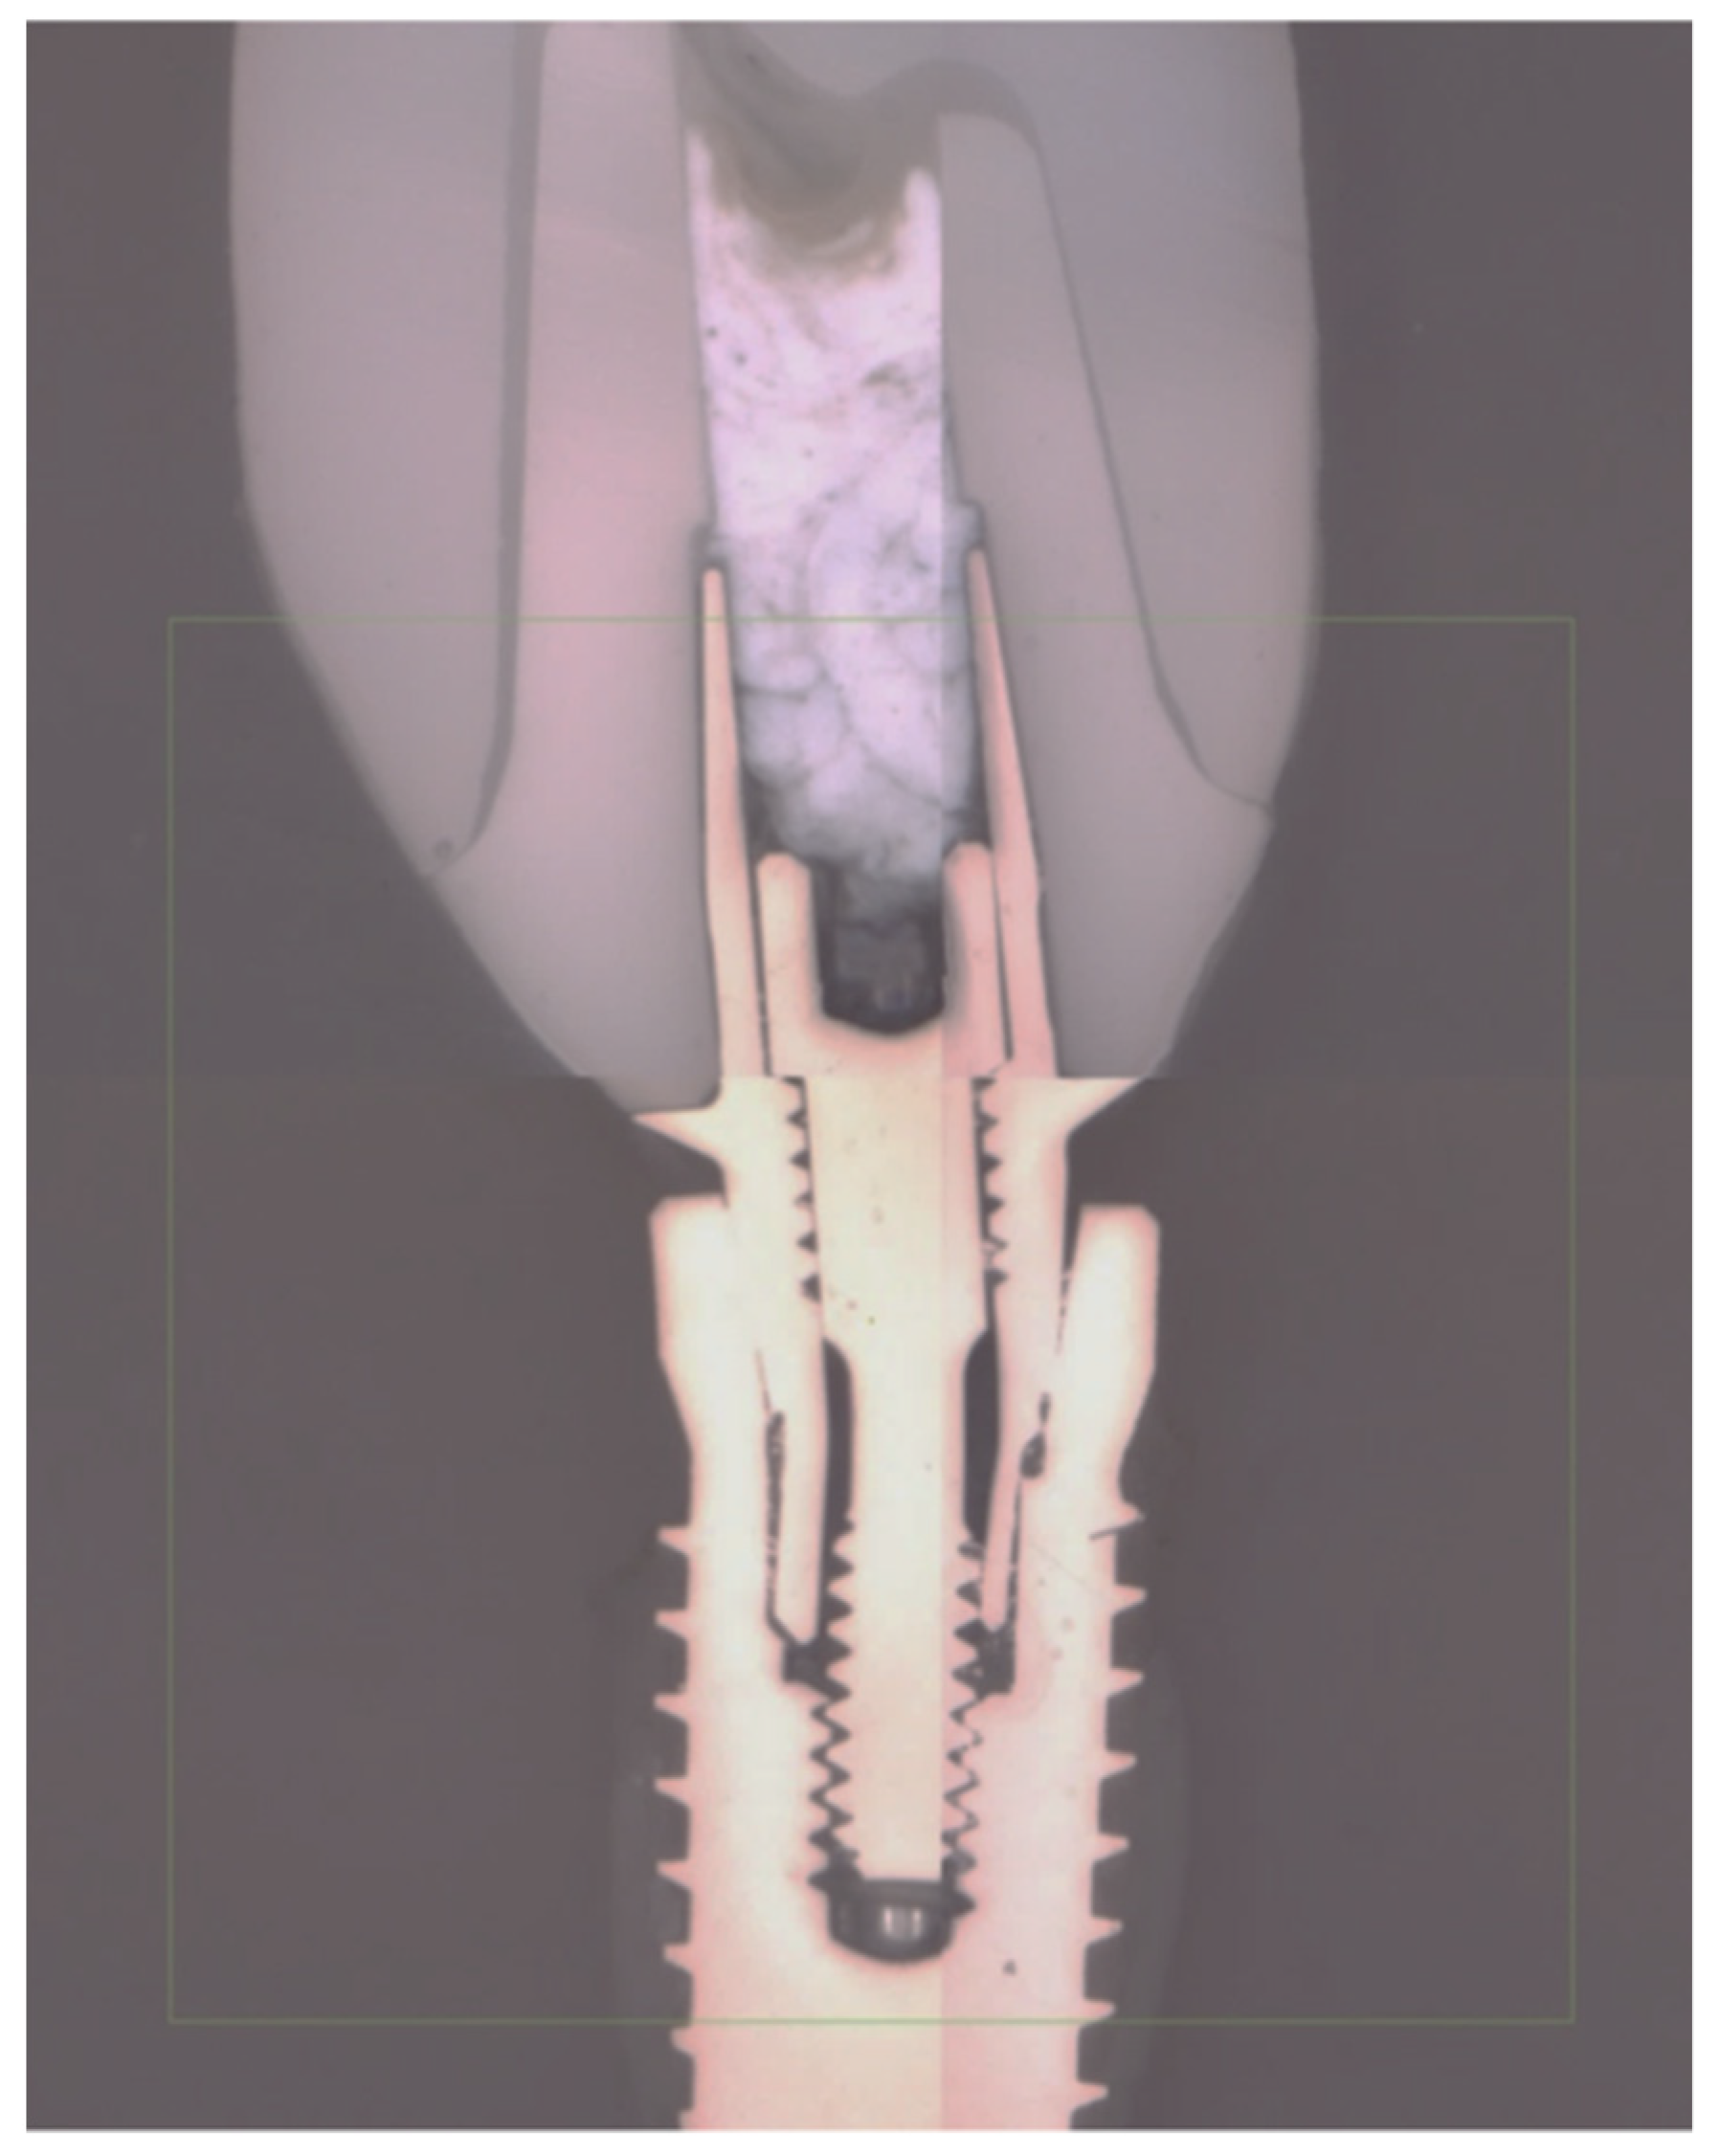

2.4. Macro and Micro Structural Analysis

3.3. Failure Modes

3.4. Finite Element Analysis